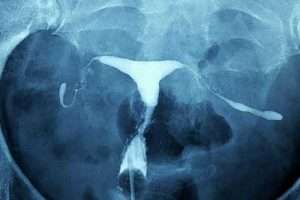

Myom

Rahim sağındaki iri myom kitlesi rahim boşluğu alt kısmının uzamasına ve sola doğru itilmesine sebep olmuş.